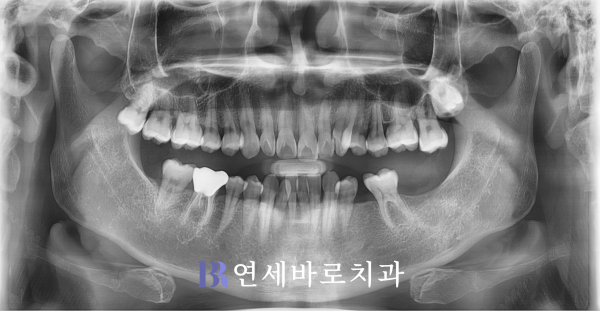

지금부터 알아볼 환자분께서는

영구치 소실로 임플란트가

필요하다면서 찾아오셨습니다.

왼쪽의 제2대구치와 더불어

그 앞의 작은 어금니가 빠져

매식체를 식립해야 할 필요가

있는 것으로 판단되었습니다.